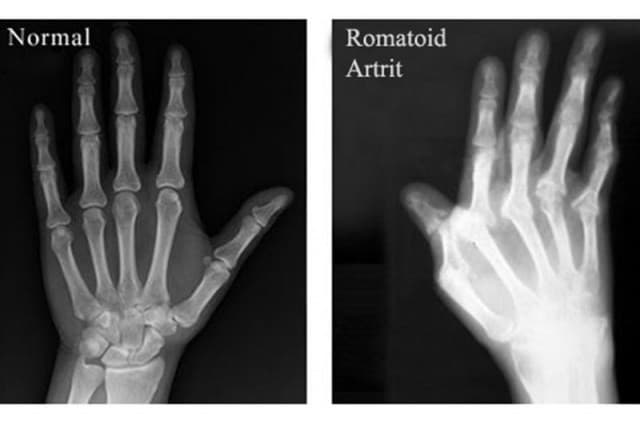

Hình ảnh khớp bình thường và viêm khớp dạng thấp

Viêm khớp dạng thấp là bệnh lý khá phổ biến trên thế giới, đây là tình trạng viêm mô hoạt dịch ở khớp, kéo dài gây ăn mòn xương, phá hủy sụn và làm mất toàn bộ cấu trúc khớp.

Viêm khớp dạng thấp nếu không được chẩn đoán và điều trị sớm có thể gây tàn phế vĩnh viễn.